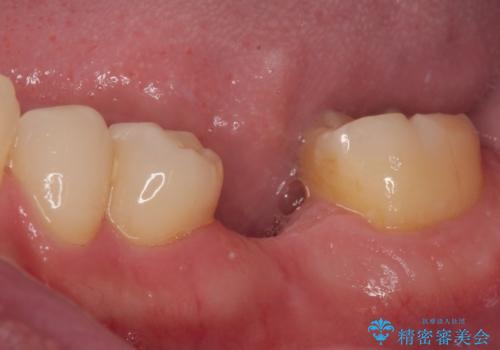

放置した欠損部 奥歯の即時荷重インプラント治療

- 左下欠損部のインプラント治療を希望して来院された患者様です。

左下の欠損部を長期間欠損を放置していたことで、咬み合う上の奥歯が動いてしまっている状態でした。

インプラント部は埋入とともに仮歯を装着し、同時に上顎奥歯の部分矯正を開始することとしました。